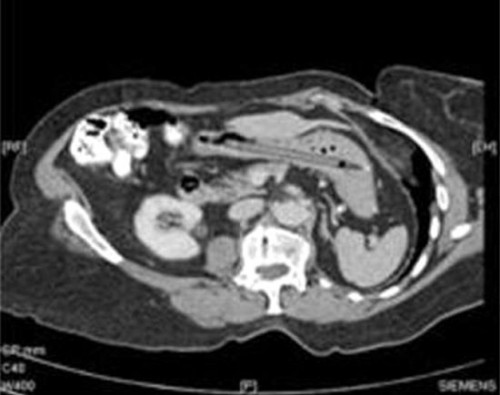

This story has all the makings of a wonderful ad campaign for the pen manufacturer. A woman accidentally swallowed a pen. Her husband and doctor thought that she was making the whole thing up, so nothing was done about it. Twenty-five years later, a surgeon removed it from her and found the pen in full working order.

Link -via DVICE | Photo: British Medical Journal/Oliver Richard Waters, Tawfique Daneshmend, Tarek Shirazi